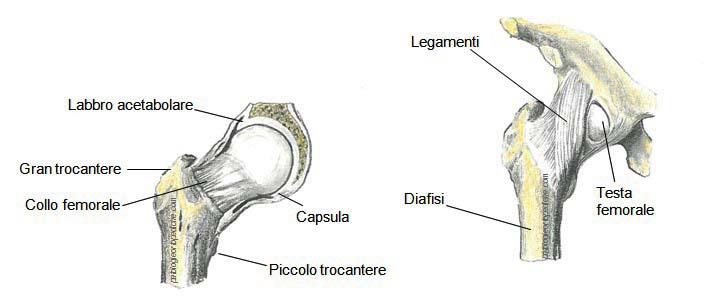

- L’articolazione dell’anca